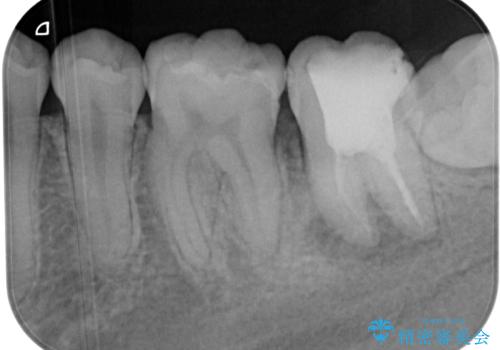

- 食事などで噛んだときに奥歯に痛みを感じるとのことで来院された患者様です。

奥に埋もれている親知らずが原因でむし歯になり、以前に根管治療を行った歯が痛みの原因であり、再度根管治療が必要な状態でした。

根管治療を行った歯は原則としてクラウンによる補綴治療が必要となるため、事前に親知らずを抜歯し、その後根管治療を行うこととしました。

歯根先端付近の歯槽骨が溶けてるレントゲン像が認められましたが、治療から半年後のレントゲン写真では、消退している様子が認められました。